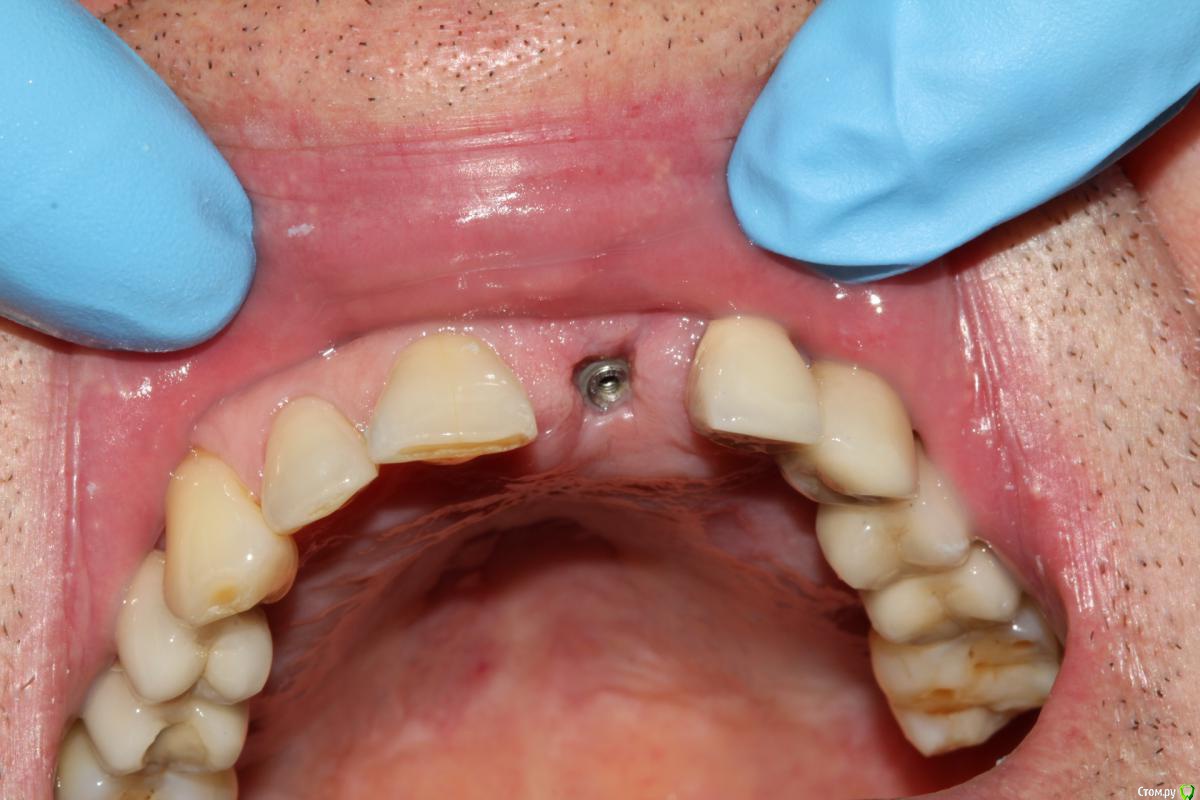

Muhamedgaliev Опубликовано 30 июня, 2017 Поделиться Опубликовано 30 июня, 2017 Доброго времени суток коллеги. 2 недели назад производил имплантацию. Удалил, закрутил(Ankilos), ССТ с бугра, хотел временную конструкцию установить, но не удалось(не правильно выбрал абатмант), заглушил, ушился. Вот такая картина через 2 недели. Имплант виднеется, витка три. И внимание вопрос) Что делать?)) Кто с талкивался с таким клиническим случаем... Ссылка на комментарий

Иван911 Опубликовано 1 июля, 2017 Поделиться Опубликовано 1 июля, 2017 Там на имплантоводе должна быть отметка, обычно 3мм, по ней ориентируйтесь от края слизистой, это минимум. Анкилоз лучше еще глубже чем 3. Здеь я бы выкрутил, промыл и одномоментно вкрутил глубже уже либо с стандартным формирователем, либо индивидуальным. Ссылка на комментарий